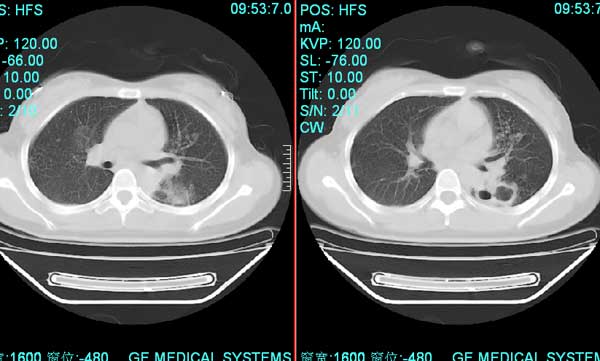

以下是引用pujunzhi在2008-7-1 20:03:00的发言:[br]支持楼主意见!两肺继发性肺结核伴多发空洞形成。